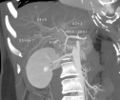

يتميز الكبد من باقي أعضاء البدن بأن ترويته الدموية تتم عن طريقين: طريق وريد الباب الذي يجلب نحو سبعين بالمئة من الدم الذي يدخل إلى الكبد، والشريان الكبدي الذي يجلب قرابة ثلاثين بالمئة من الدم. ينقسم وريد الباب في سرة الكبد إلى فرعين أيمن وأيسر يتفرعان بدورهما إلى فروع أصغر فأصغر تروي قطع الكبد الثمان. كما ينقسم الشريان الكبدي أيضاً في سرة الكبد إلى فرعين أيمن وأيسر يسيران بمحاذاة فروع وريد الباب حتى الشعب الانتهائية. يخرج الدم من الكبد بعد إروائه عن طريق الأوردة الكبدية وعددها ثلاث تصب كلها في الوريد الأجوف السفلي. تجمع الشعيراتُ الصفراوية الصفراءَ التي تفرزها الخلايا الكبدية، وتنضم هذه الشعيرات بعضها إلى بعض لتشكل قنيات صفراوية. تتحد هذه القنيات فيما بينها لتشكل قناتين صفراويتين يمنى ويسرى تلتقيان في سرة الكبد فتؤلفان القناة الكبدية الرئيسة. تسير هذه الأقنية الصفراوية جميعها داخل الكبد وخارجه بمحاذاة وريد الباب والشريان الكبدي وفروعهما.

الجزء المركزي وتوجد به القناة الصفراوية الرئيسية والشريان الكبدي البابي وكذلك الوريد الكبدي البابي وهؤلاء الثلاثة يدخلون في تجويف في مركز الكبد يسمى الهيلم أو الباب الكبدي porta hepatis -Hilum

كلا من الأوعية الثلاثة السابق ذكرهم ينقسم بدوره الى فرعين يمين ويسار حتى يقوموا بتغذية كلا الفصين الأيمن و الأيسر.

يقوم الشريان الكبدي الأيمن بتقسيم الفص الأيمن من الكبد الى قطاعين أمامي وخلفي.anterior and posterior segments

بينما يقسم الشريان الكبدي الايسر الفص الكبدي الايسر الى قطاعين هما الأوسط والجانبي medial and lateral segments

وطبقا للتقسيم الفرنسي المستعمل بكثرة في التقسيم الوظيفي للكبد فانه ينقسم الى ثمانية قطاعات صغيرة بناء على الفرع الشرياني الذي يغذي كل منهم في حين أن الفص الذيلي caudate lobe هو قطاع منفصل عن باقي القطاعات حيث أنه يتميز عنهم بأنه يتغذى عل كل من الشريان اليمينى واليساري الكبدي